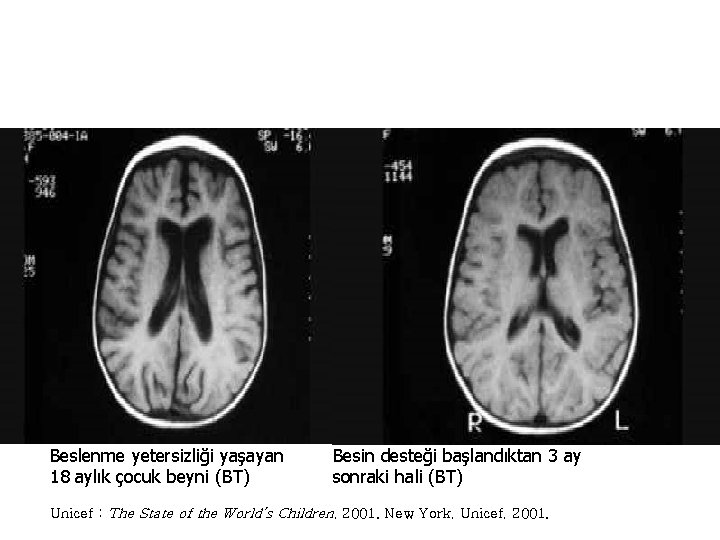

Beslenme yetersizliği yaşayan 18 aylık çocuk beyni (BT) Besin desteği başlandıktan 3 ay sonraki hali (BT) Unicef : The State of the World’s Children, 2001. New York, Unicef, 2001.